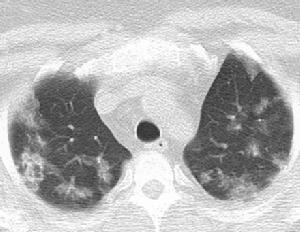

影像學表現:雙肺瀰漫性大片狀實變,分布不均勻,其內見小囊狀透亮區呈蜂窩狀改變;實變陰影之間可見不規則片狀透亮區,可見索條狀背景,表現大片狀肺實變與大片狀代償肺氣腫並存;雙肺門明顯濃大,結構不清;心外形正常,雙側膈頂光整正常,雙側肋膈角正常。

3、胸部CT/HRCT檢查 PAP的X線胸部檢查無特異性,不能有效地將PAP與卡氏肺孢子蟲肺炎(PCP)、IPF等區分開。新出現的CT和HRCT為PAP的診斷提供了一個有效的手段。典型的PAP在CT上表現為肺部多變的斑片狀陰影,其邊緣清楚,在肺野中呈地圖樣表現。PAP在HRCT中則呈現出毛玻璃樣改變,小葉內和小葉間隙增厚,因其邊緣為多邊形,故呈碎石路樣改變(Crazy-Paring)。這些表現有一定的特徵性,雖然其有時也可見於PCP和肺結節病,但通過詢問病史和對臨床表現進行分析,就可予以區分。本文9例中有3例作CT/HRCT檢查,結果與文獻報導相似。因此,可以認為將病史、臨床表現和CT/HRCT檢查結合起來,大部分PAP病人不必進行肺活檢及BALF檢查即可診斷。